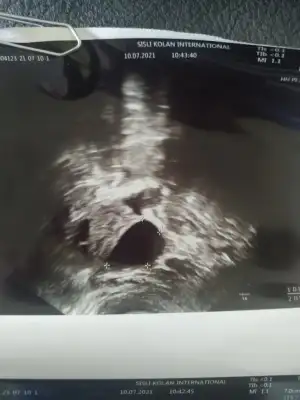

keseyi gördü ama boş tabi daha jkahsdkja salı yine gitcem bayram sonunda da kalp atışını çok rahat duyarız dedi. geç döllenme değil dedi son regl tarihinle uyumlu dedi 4-5 gün sapma var ama o da normal dedi (geç yumurtlamıştım) 6 mart gibi doğum beklerim dedi.. iç tarafta kanama falan yokmuş duvar kısma yapışmış bebecik ama sol tarafta bir kist var o 4 aya kadar erimezse sıkıntı dedi nolcak bilemiyorum. kalp hastası olduğumdan tansiyon sıkıntılı onu beğenmedi salı kardiyolojiyle de bir ortak bakacaklarmış..